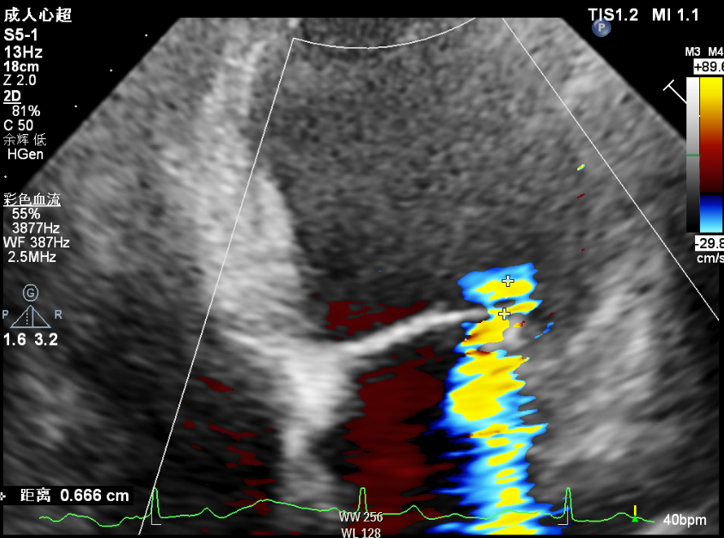

手术采用左侧第六肋间微创切口心尖入路,在超声引导下,清晰识别MitraFix®输送系统准确跨瓣,并将人工瓣膜准确释放于二尖瓣瓣环,瓣膜释放后支架贴合牢固,无瓣周漏及瓣内返流,二尖瓣前向血流通畅,左心室流出道通畅,流出道血流速度为1.6 m/s. 顺利撤出输送系统,关闭心尖切口几乎无出血,手术顺利结束。术后当天下午监护室顺利拔除气管插管。

术前反流

术后无瓣周漏